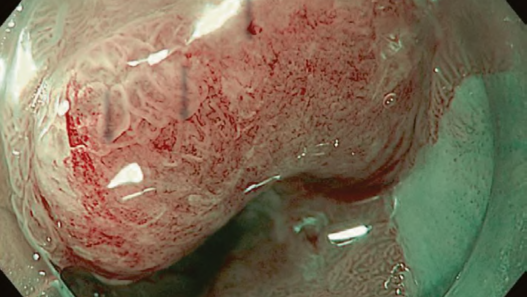

The working group members carried out a systematic review of the English literature to determine widely accepted diagnostic systems. Consequently, the best-accepted diagnostic system was proven to be the VS classification system. Based on this system, MESDA-G was constructed using an evidence-based approach (. Figs. 3, 4, 5, and 6) [2]. First, lesions suspicious for EGC should be detected by careful inspection using conventional white-light endoscopy. Subsequently, magnified observations should be performed. Owing to the high sensitivity of the demarcation line [8], if it is absent, the suspicious lesion is diagnosed as noncancerous (. Fig. 4a, b). However, if the demarcation line is present, further assessment is required to determine the presence of an irregular MV or MS pattern. If an irregular MV and/or MS pattern is detected, the suspicious lesion is diagnosed as cancerous (. Fig. 6a, b) [1, 5, 6, 8]. If both the irregular MV and MS patterns are absent, the tumor is diagnosed as noncancerous (. Fig. 5a, b) [1, 5, 6, 8].